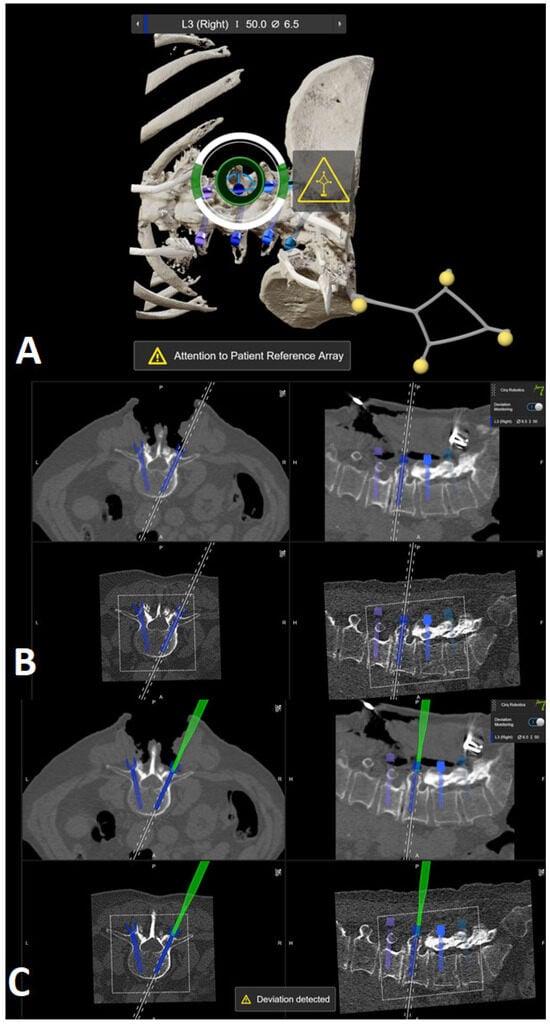

The kinematic unit of the Cirq® Robotic Alignment Module with the previously calibrated tracking array is positioned over the projection of the screw entry point. The instruments are tracked in real time, and their position is constantly reported back so that the surgeon can observe the movements of the robotic arm and all instruments on a separate monitor. The surgeon is located on the side of the robotic arm, i.e., on the left side of the patient. After positioning the robotic arm over the projection of the trajectory entry point, the robotic arm automatically aligns itself according to preplanned trajectory of the relevant screw. In percutaneous cases, a previously calibrated and registered trocar can be used to open the soft tissue for screw implantation, followed by the attachment of an instrument holder for the drill guide. A drill guide is then inserted through the tracking array with the instrument holder and positioned at the entry point, and attachable snap-on depth control for drilling is then attached. The tracking array is then locked, and drilling begins. In this step, it is crucial that the surgeon additionally stabilizes the instrument holder with sufficient pressure on the entry point to prevent skiving. A K-wire is implanted, and the robotic arm is removed. This workflow is repeated for all trajectories. All K-wires are secured to the cover with clamps to keep them in place. (Figure 10, Figure 11, Figure 12, Figure 13 and Figure 14) [4].

Figure 14. (A) Position of the robotic arm when the rough projection of the entry point of preplanned screw trajectory (in this case, the right L3 screw) is reached. The circle representing the kinematic unit of robotic arm turns green, and then the surgeon can release the robotic arm, which then automatically aligns itself according to the preplanned trajectory. (B) End position of the trajectory along the preplanned screw in the axial and sagittal view of iCT and preoperative CT. (C) Position of the drill guide instrument holder with a tracking array of the robotic arm, which can be securely locked after correct placement at the entry point. The system is very sensitive, so deviations from the original plan are reported very frequently, although these deviations are in the range of 1–2 mm.